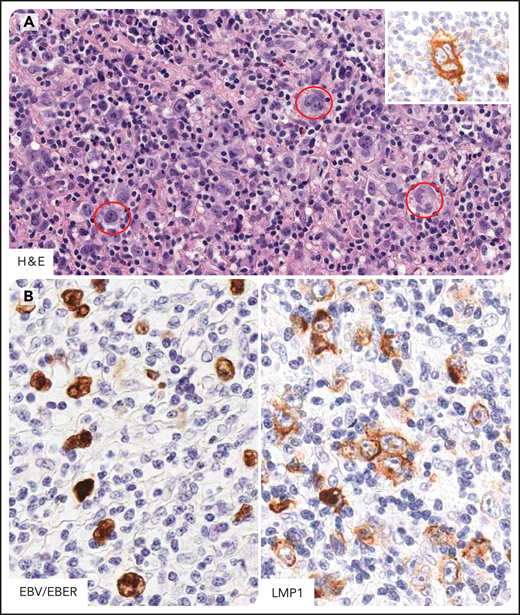

HL in individuals infected by HIV. Hodgkin and Reed-Sternberg cells (HRS) in HL of individual infected by HIV express CD15, CD30, CD40, and MUM1/IRF4 and LMP1 (EBV-type II latency) (A) Several HRS cells are seen (in the red circle) within a mixed inflammatory microenvironment. These cells express CD30 (inset). (B) EBV-infected tumor cells are demonstrated by EBER in situ hybridization and LMP1 immunostaining. CD30 and LMP1, immunohistochemistry, hematoxylin counterstain; EBER, in situ hybridization, nuclear fast red counterstaining. Original magnification, ×400. Images were taken using a Nikon Eclipse 80i microscope with a Plan Fluor 40×/0.75 objective and Nikon digital sight DS-Fi1 camera equipped with control unit-DS-L2. Images were processed using Adobe Photoshop 6.